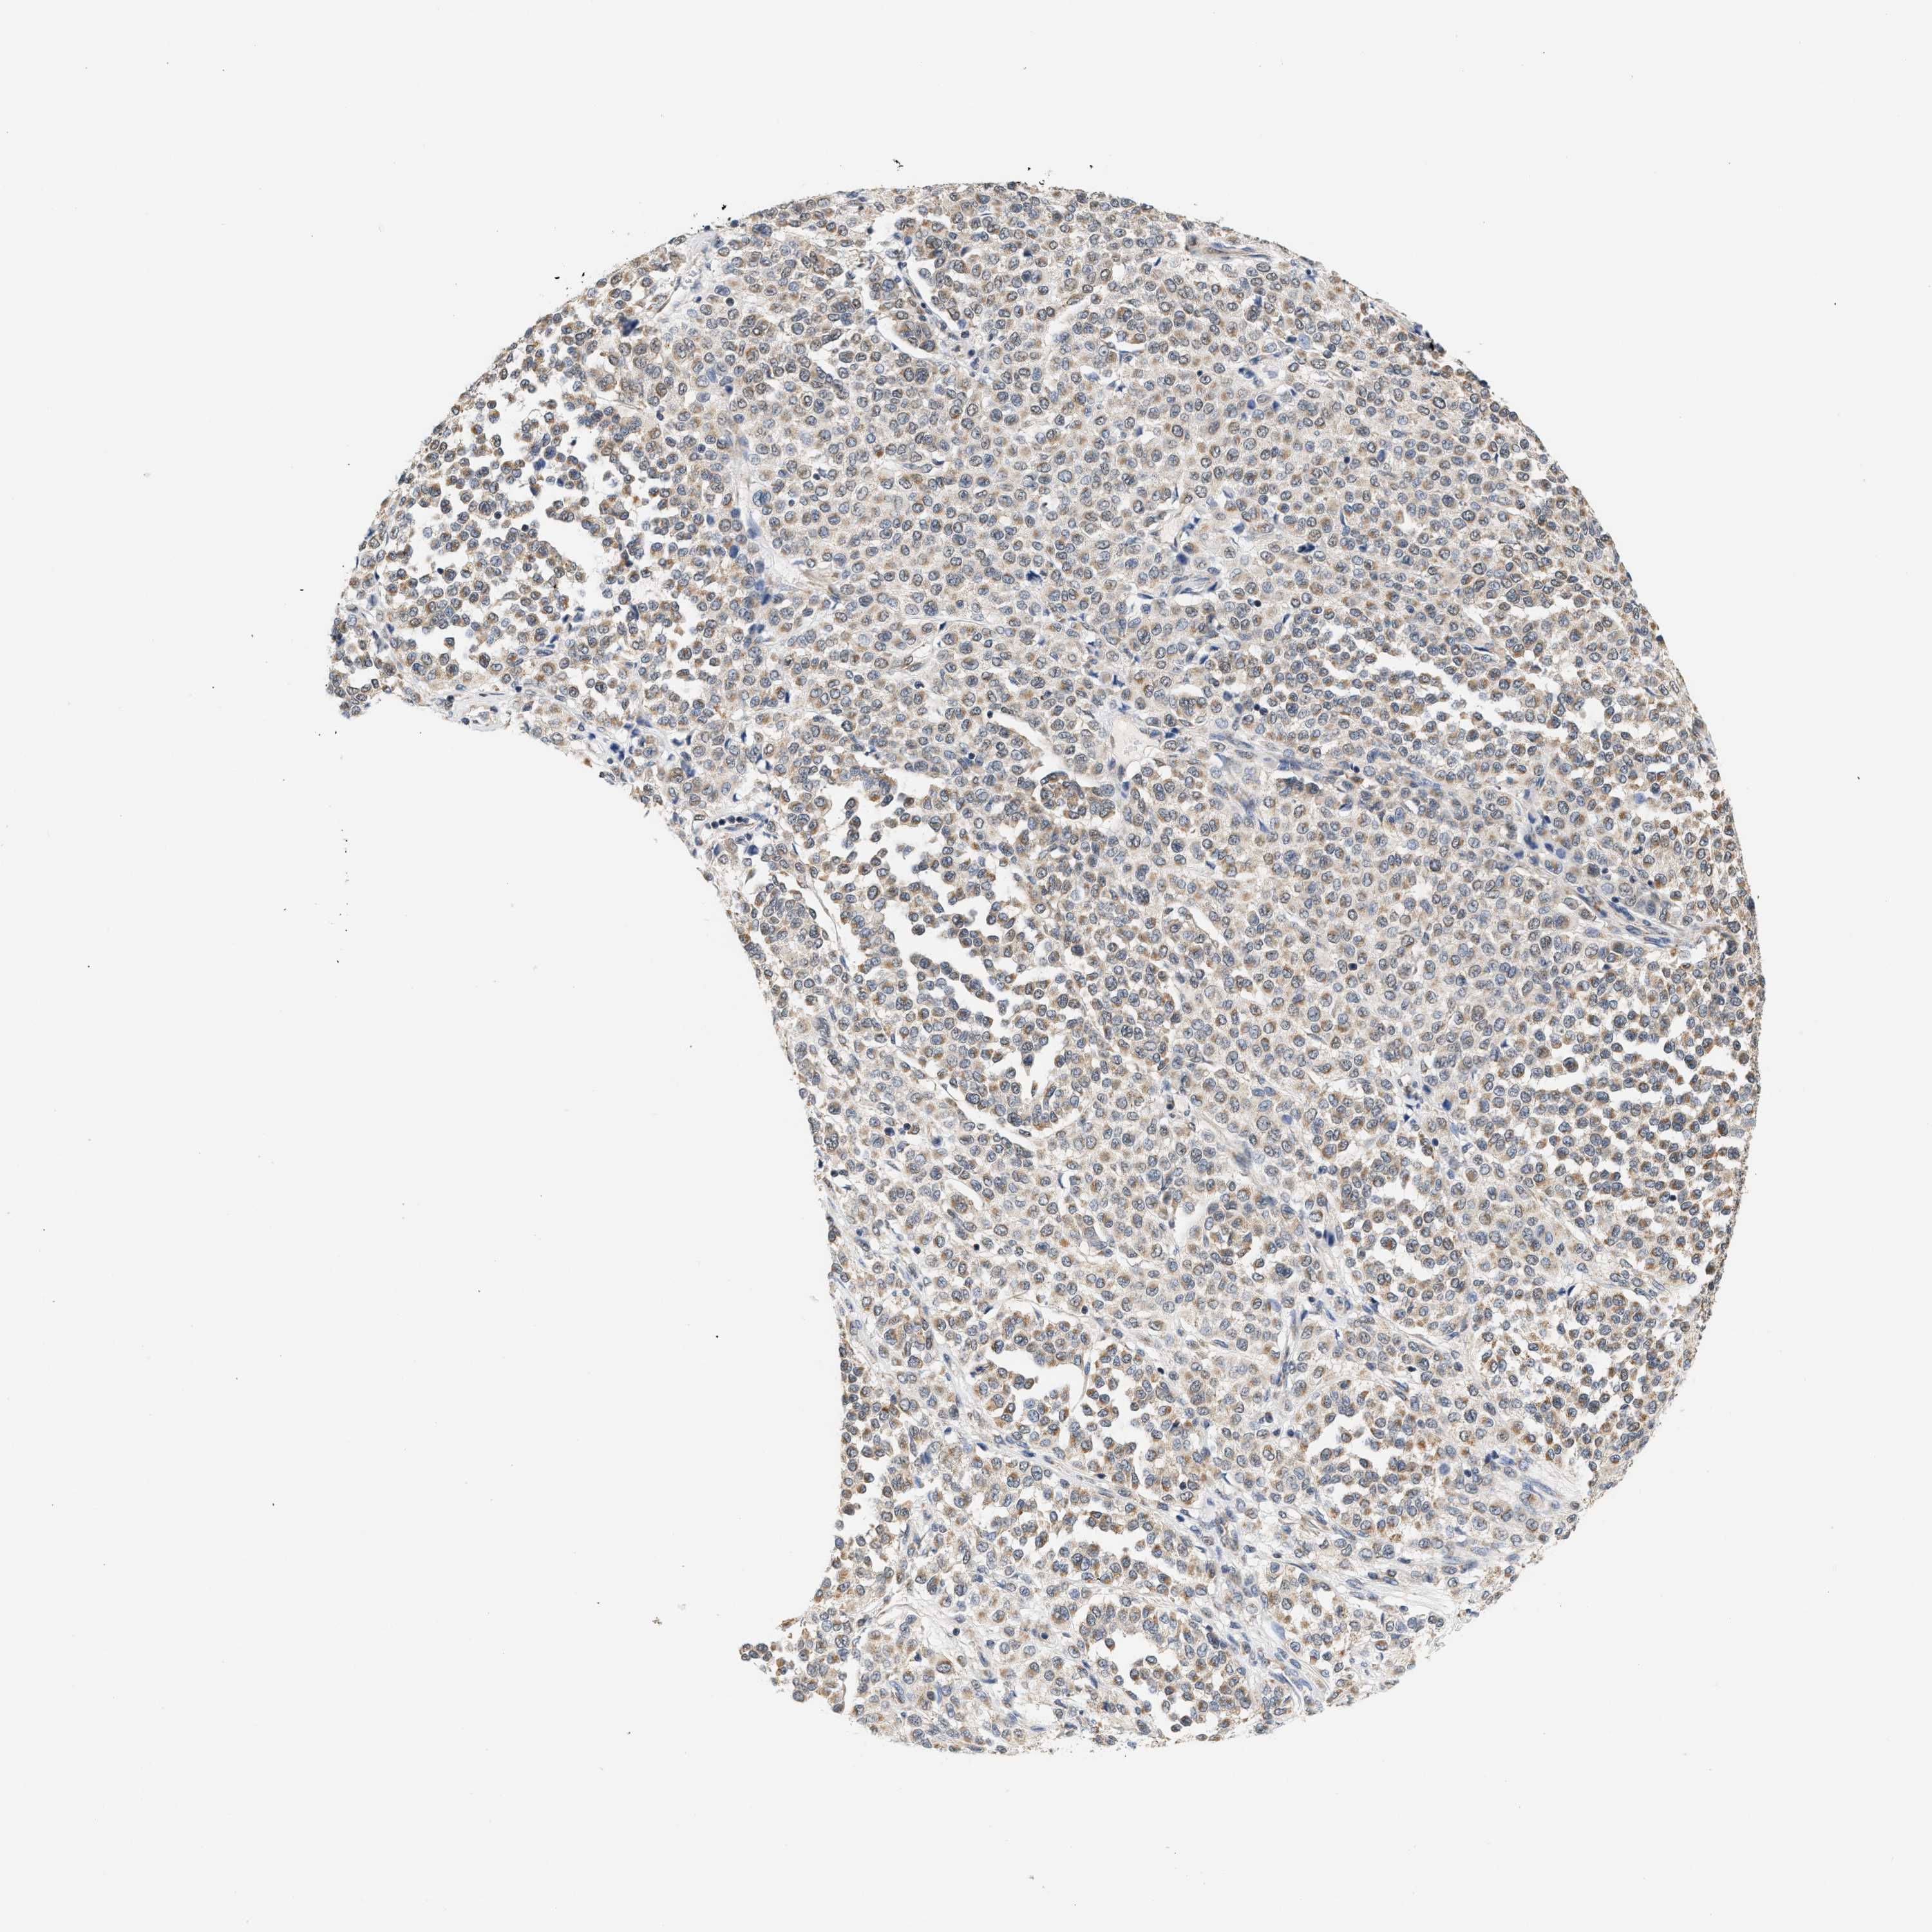

MELANOMA - Protein expressioni

A mouse-over function shows sample information and annotation data. Click on an image to view it in a full screen mode. Samples can be filtered based on level of antibody staining by selecting one or several of the following categories: high, medium, low and not detected. The assay and annotation is described here.

Note that samples used for immunohistochemistry by the Human Protein Atlas do not correspond to samples in the TCGA dataset.

Antibody stainingi

Antibody staining in the annotated cell types in the current human tissue is reported as not detected, low, medium, or high, based on conventional immunohistochemistry profiling in selected tissues. This score is based on the combination of the staining intensity and fraction of stained cells.

Each image is clickable and will lead to virtual microscopy that enables deeper exploration of all samples and also displays staining intensity scores, fraction scores and subcellular localization as well as patient and tissue information for each sample.

Antibody HPA020999

Antibody HPA023995

Staining

High

Medium

Low

Not detected

Intensity

Strong

Moderate

Weak

Negative

Quantity

>75%

75%-25%

<25%

None

Location

Nuclear

Cytoplasmic/membranous

Cytoplasmic/membranous,nuclear

Malignant melanoma, NOS

Malignant melanoma, Metastatic site